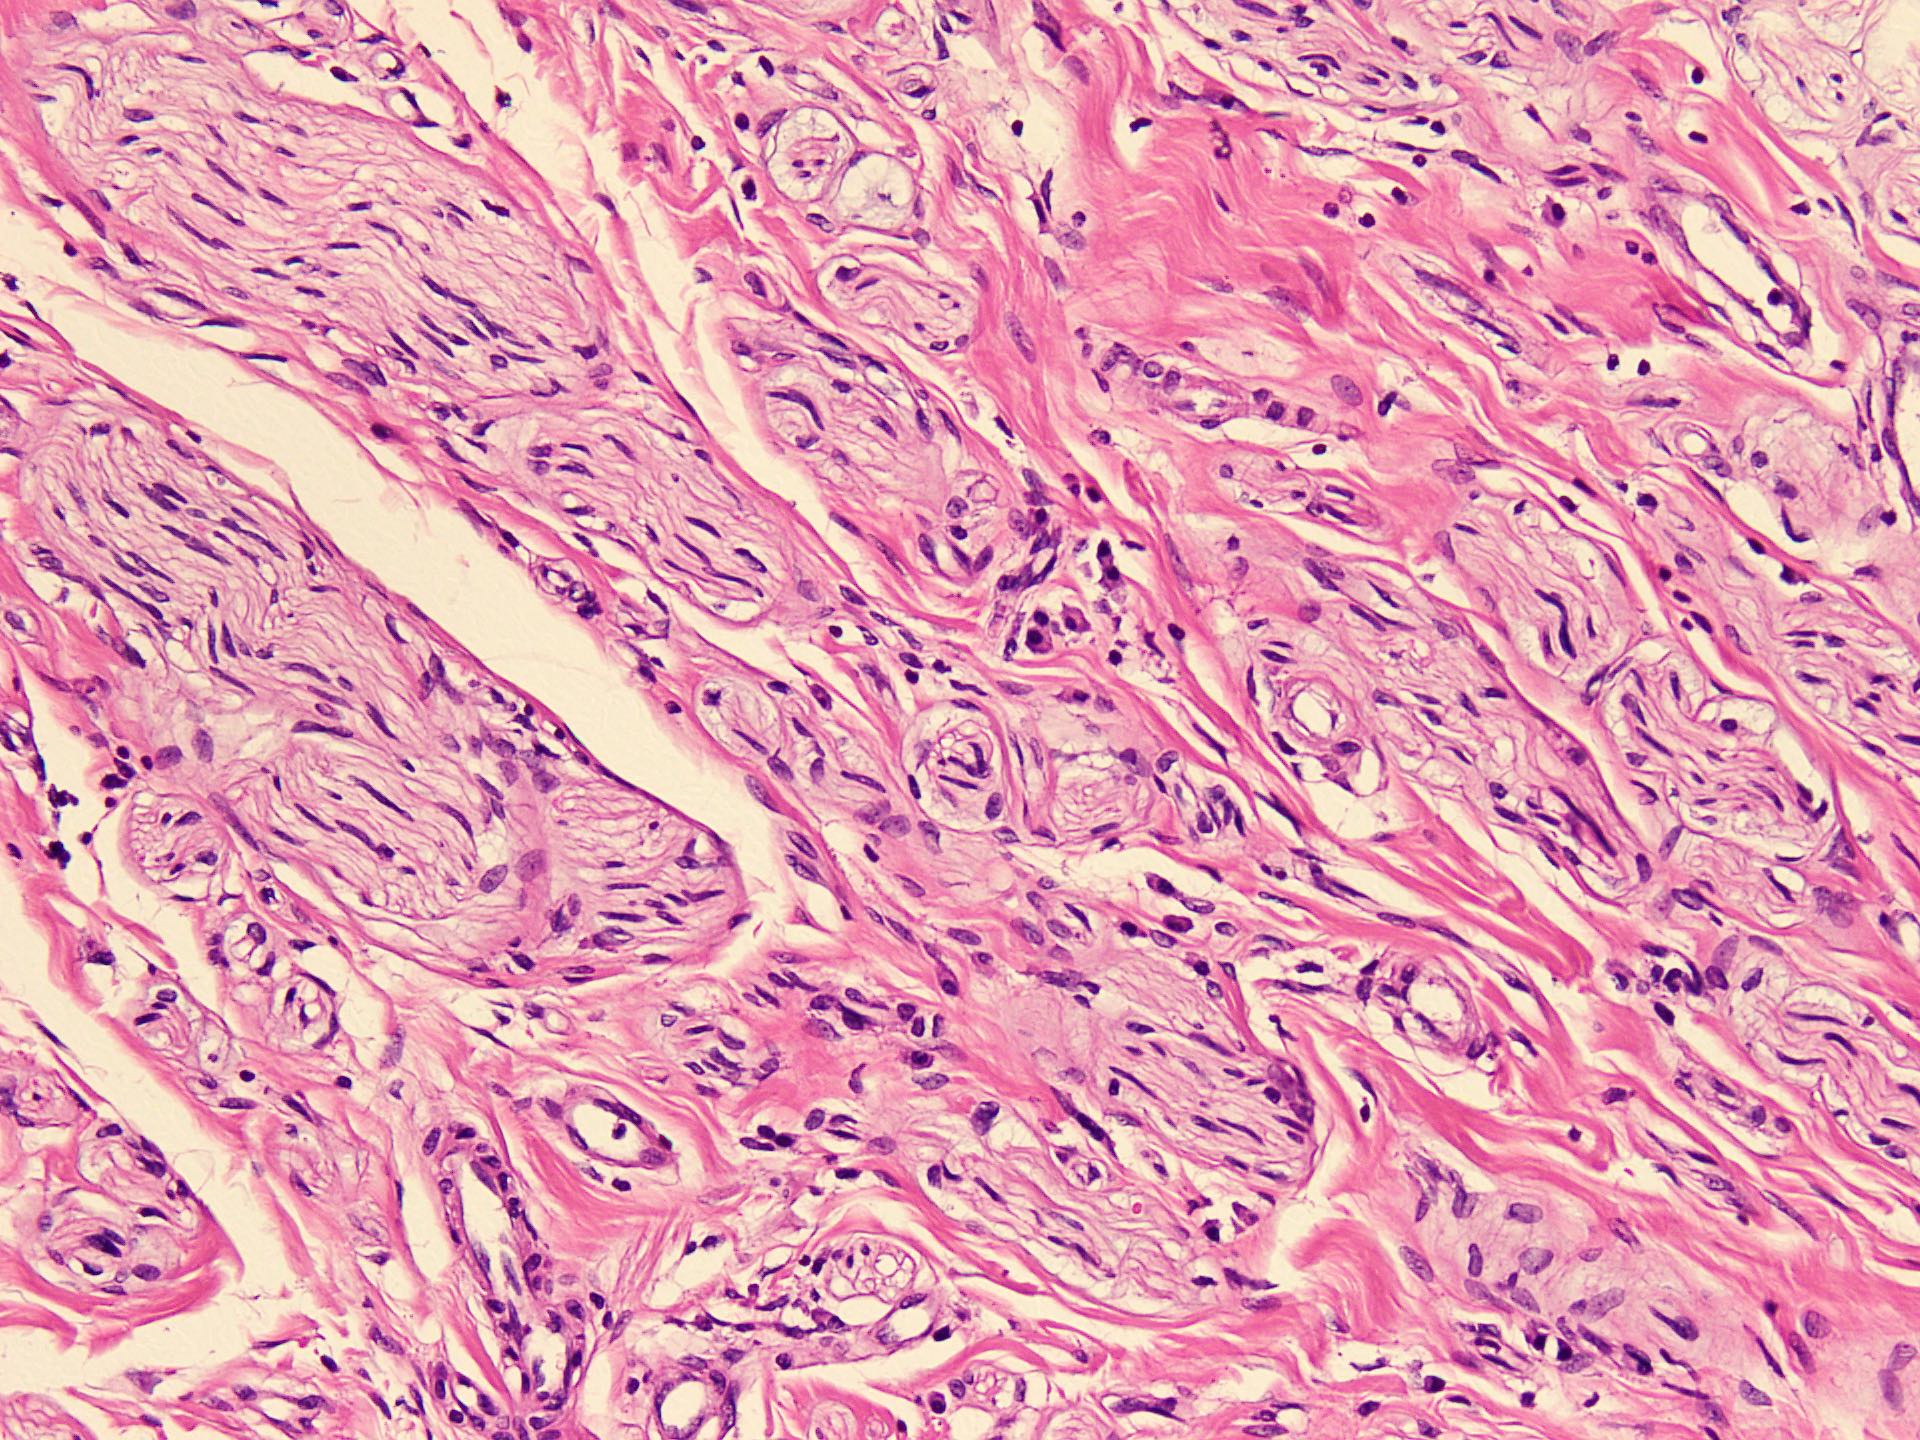

Microscopic (histologic) description

- Circumscribed, unencapsulated spindle cell proliferation arranged in short bundles comprised of axons, Schwann cells, endoneurial cells and perineurial cells (World J Clin Cases 2020;8:3821, Acta Biomed 2020;91:122, StatPearls: Neuroma [Accessed 21 September 2022])

- Peripheral palisading is not present (World J Clin Cases 2020;8:3821)

- Prominent scar tissue with dense collagen may be present (Acta Biomed 2020;91:122, StatPearls: Neuroma [Accessed 21 September 2022])

- Dystrophic calcifications are rarely present (Acta Biomed 2020;91:122)

Microscopic (histologic) images

- Microscopy: The sections examined show a circumscribed, unencapsulated lesion composed of variable sized, closely packed nerve bundle along with scar tissue in the background.

A patient presented with a painful nodule that developed after an amputation of the left first finger. On examination, the nodule is painful. Excision of the lesion is performed which shows the histology above. Which of the following is the most likely diagnosis?